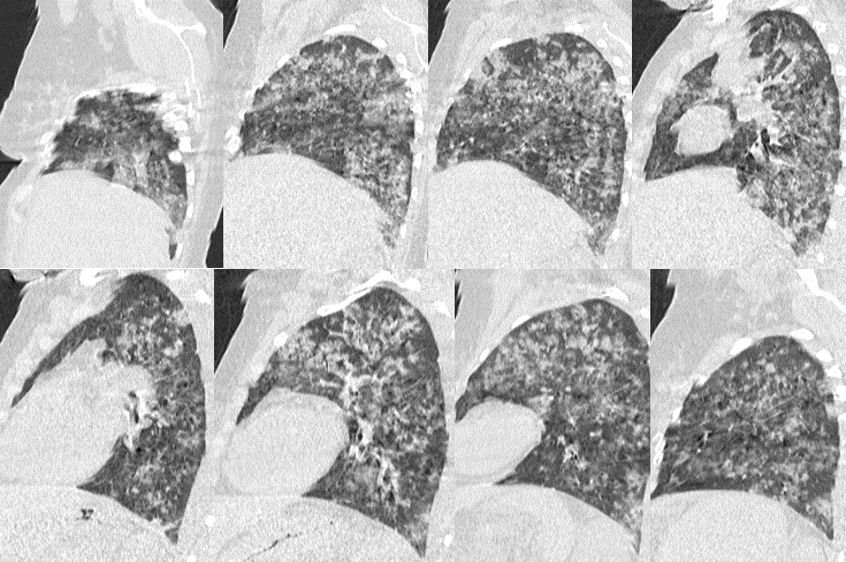

Femme, 45 ans, Suivie pour LAM depuis un mois

Hospitalisée depuis une semaine pour une chimiothérapie d’induction (Aracytine + anthracycline)

Bilan à l’admission

GB: 173 190/ul, Hb: 6g/dl, Pq: 30 000/ul, CRP: 202mg/L, TP: 57%

Apres 5 jours:

Dyspnée stade IV sans douleurs thoraciques, Hémoptysie de grande abondance

Apyrétique, SaO2: 84% , TA: 12/8, FC: 120 bpm, FR: 30

QUEL EST VOTRE DIAGNOSTIC ?